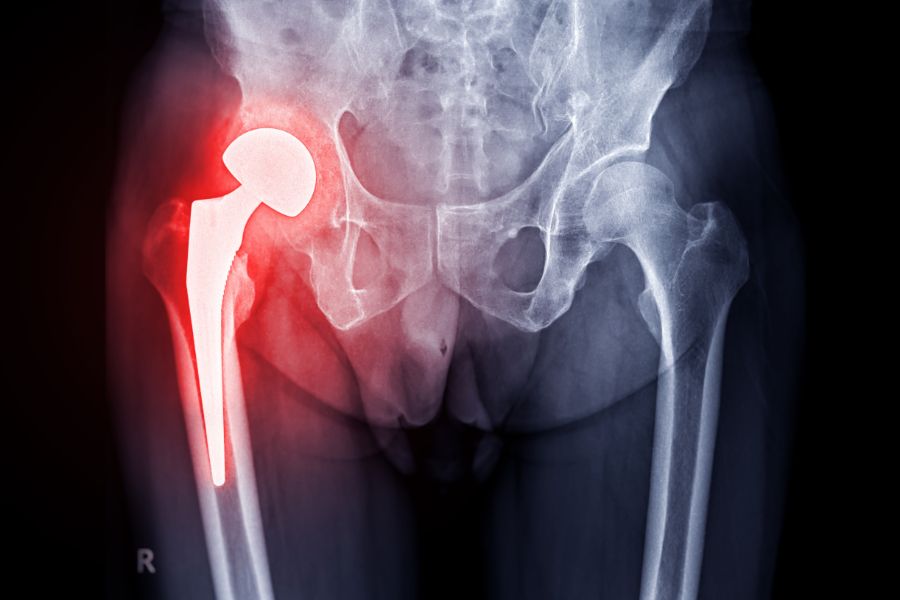

• Kalça ve Diz Protezi Cerrahisi

Kalça ve Diz Protezi Cerrahisi

Osteoartrit ve diğer dejeneratif eklem hastalıklarında, fonksiyon kaybını en aza indirmek amacıyla hastaya özel planlama ile gerek robotik ve gerekse klasik yöntemlerle kalça ve diz protez cerrahileri uyguluyoruz.

Babamın kalça kireçlenmesi nedeniyle ağrıları son dönemde dayanılmaz hale gelmişti, geceleri bile uyuyamıyordu. Sevgili Tunay hocamız başarılı bir kalça protez ameliyatı gerçekleştirdi. Babam aynı gün ayağa kalktı, şimdi torunlarıyla yürüyüşe bile çıkıyor. Böyle bir değişimi görmek bizim için mucize gibi. Güler yüzü, ilgisi ve güven veren yaklaşımı için ailecek hocama çok teşekkür ediyoruz.

İleri derecede kireçlenme yüzünden ne yürüyebiliyor ne de rahat uyuyabiliyordum. Kalça protezi ameliyatımı Doktorum Tunay Erden gerçekleştirdi. Şimdi ayağa rahatça kalkabiliyor ve istediğim kadar ağrısız yürüyebliliyorum. Tedaviniz için çok teşekkür ederim.